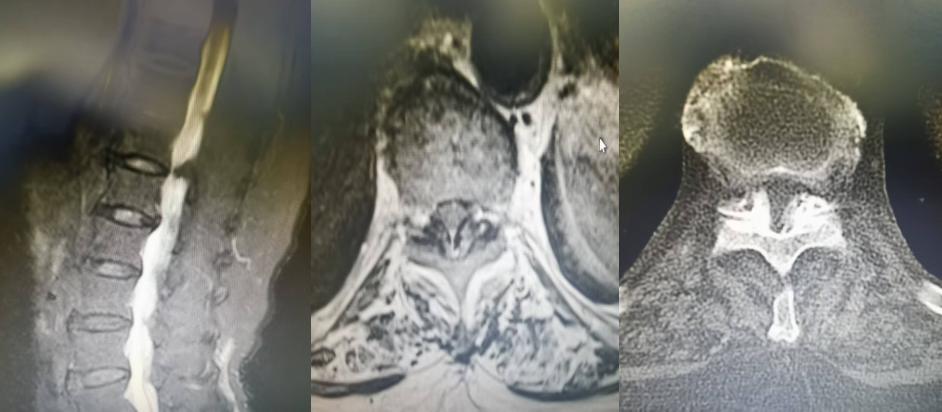

T10/11黃韌帶鈣化,椎管狹窄,硬膜囊受壓嚴(yán)重,腦脊液不通暢